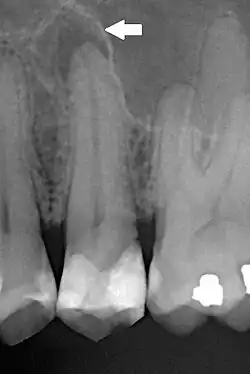

- Periodontitis apical asintomática. Inflamación y destrucción del periodonto apical, de origen pulpar, asociado con un área radiolucidez apical, y no produce síntomas clínicos. Cursa generalmente sin sintomatología o molestias leves. Los tejidos blandos colaterales no presentan ningún tipo de manifestación clínica. están dentro de los parámetros normales. Este cuadro era denominado como periodontitis irreversible crónica granulomatosa.

- Abceso apical crónico. Una reacción inflamatoria a la infección y necrosis pulpar caracterizada por su inicio gradual con poca o ninguna molestia y drenaje intermitente de pus a través de un tracto sinusal asociado (fístula). Radiográficamente se observa zona radiolúcida apical y clínicamente cursa de manera asintomática.

Los restos epiteliales de Malassez presentes en el tejido periapical, periodontal, así como en el ligamento periodontal y hueso periodontal. En las lesiones crónicas no siempre está presente, se considera la teoría de la cual pudo haber sido destruido anteriormente. La inflamación crónica rodea el tejido epitelial. La presencia de epitelio nos lleva a considerar un quiste en la región. Existe ampliamente conocido el pseudoquiste o los conceptos de quiste verdadero o no verdadero. Los patólogos orales han demostrado que radiográficamente es casi imposible determinar la diferencia entre quiste y granuloma periapical. La curación se logra con la regeneración del hueso y la reparación del periápice con cemento nuevo, en ocasiones gracias a la ayuda de la cirugía periapical.